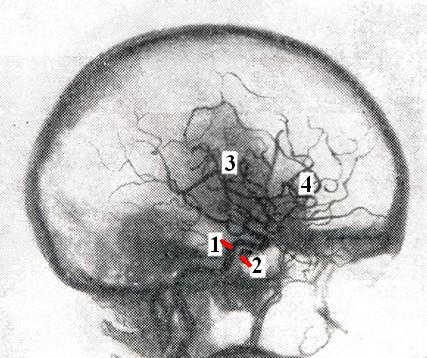

С помощью баллона окклюзируется полость кавернозного синуса, и таким образом может быть выполнена реконструкция кавернозного отдела сонной артерии (рис. 2).

Рис. 2.

Реконструкция кавернозного отдела сонной артерии при каротидно-кавернозном соустье: 1 — внутренняя сонная артерия; 2 — баллон, выключивший соустье; 3 — средняя мозговая артерия; 4 — передняя мозговая артерия.